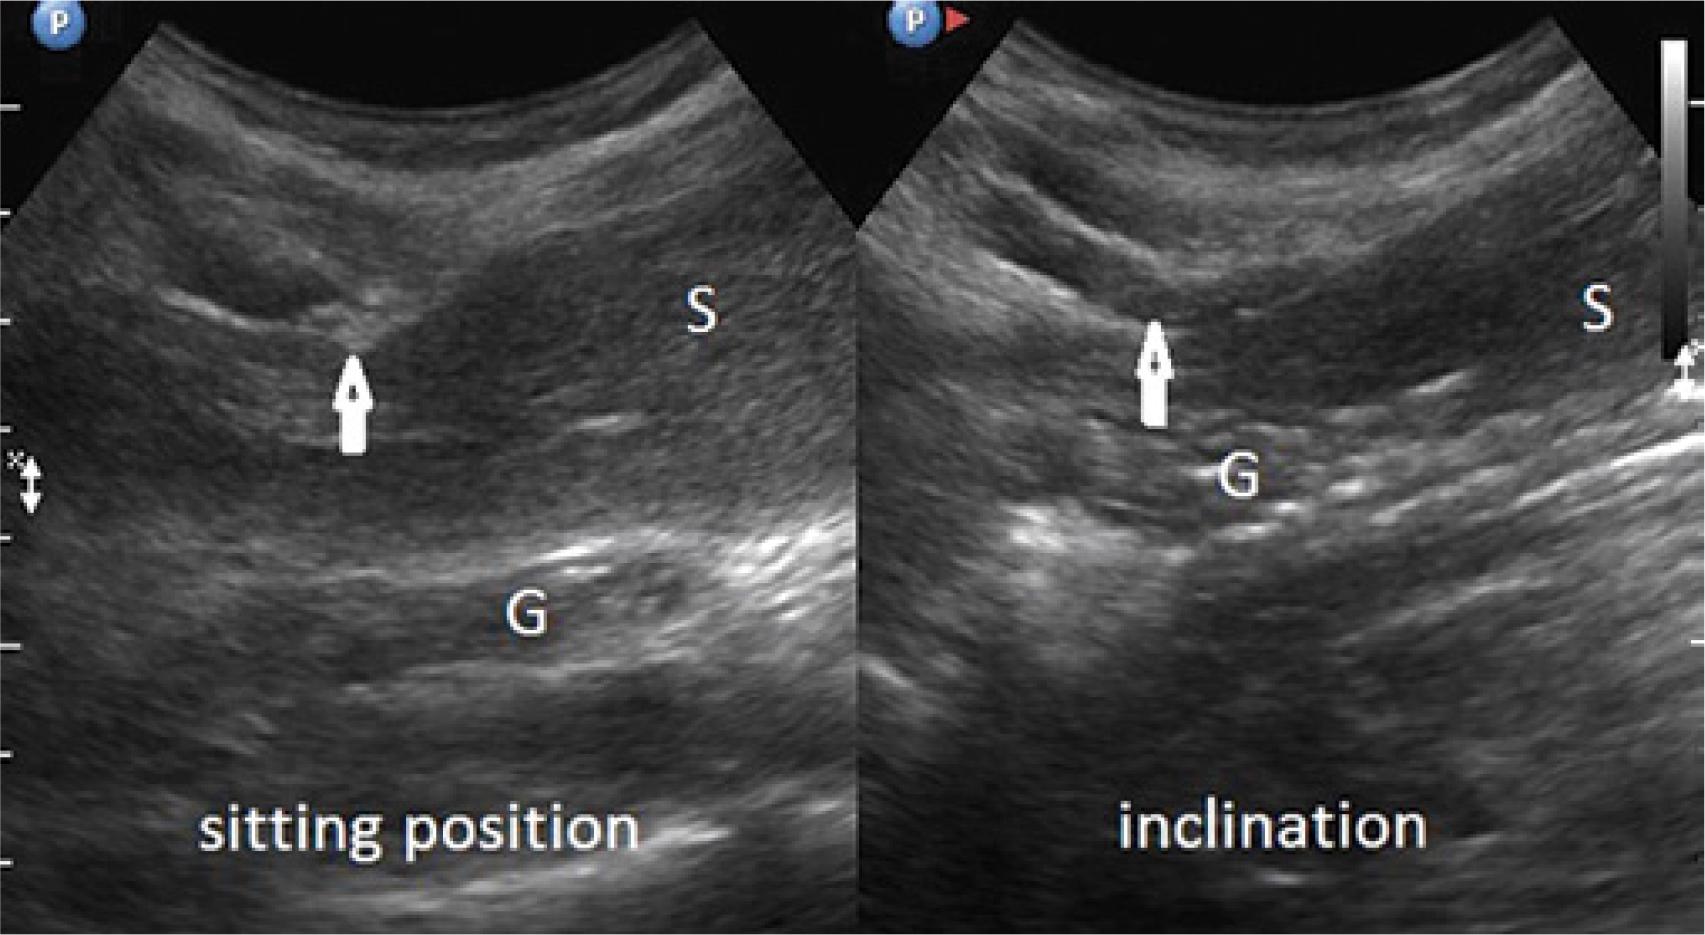

Comparison of the thickness of the musculocartilaginous complex during inhalation, exhalation, supine position, sitting position and forward trunk flexion in 178 patients

| Inhalation | 11–28 mm | 14.5 mm +/− 2.4 | Exhalation | 12–40 mm | 21.5 mm +/− 3.3 |

| Sitting | 11–31 mm | 17.0 mm +/− 2.9 | Flexion | 20–40 mm | 25.4 mm +/− 3.5 |